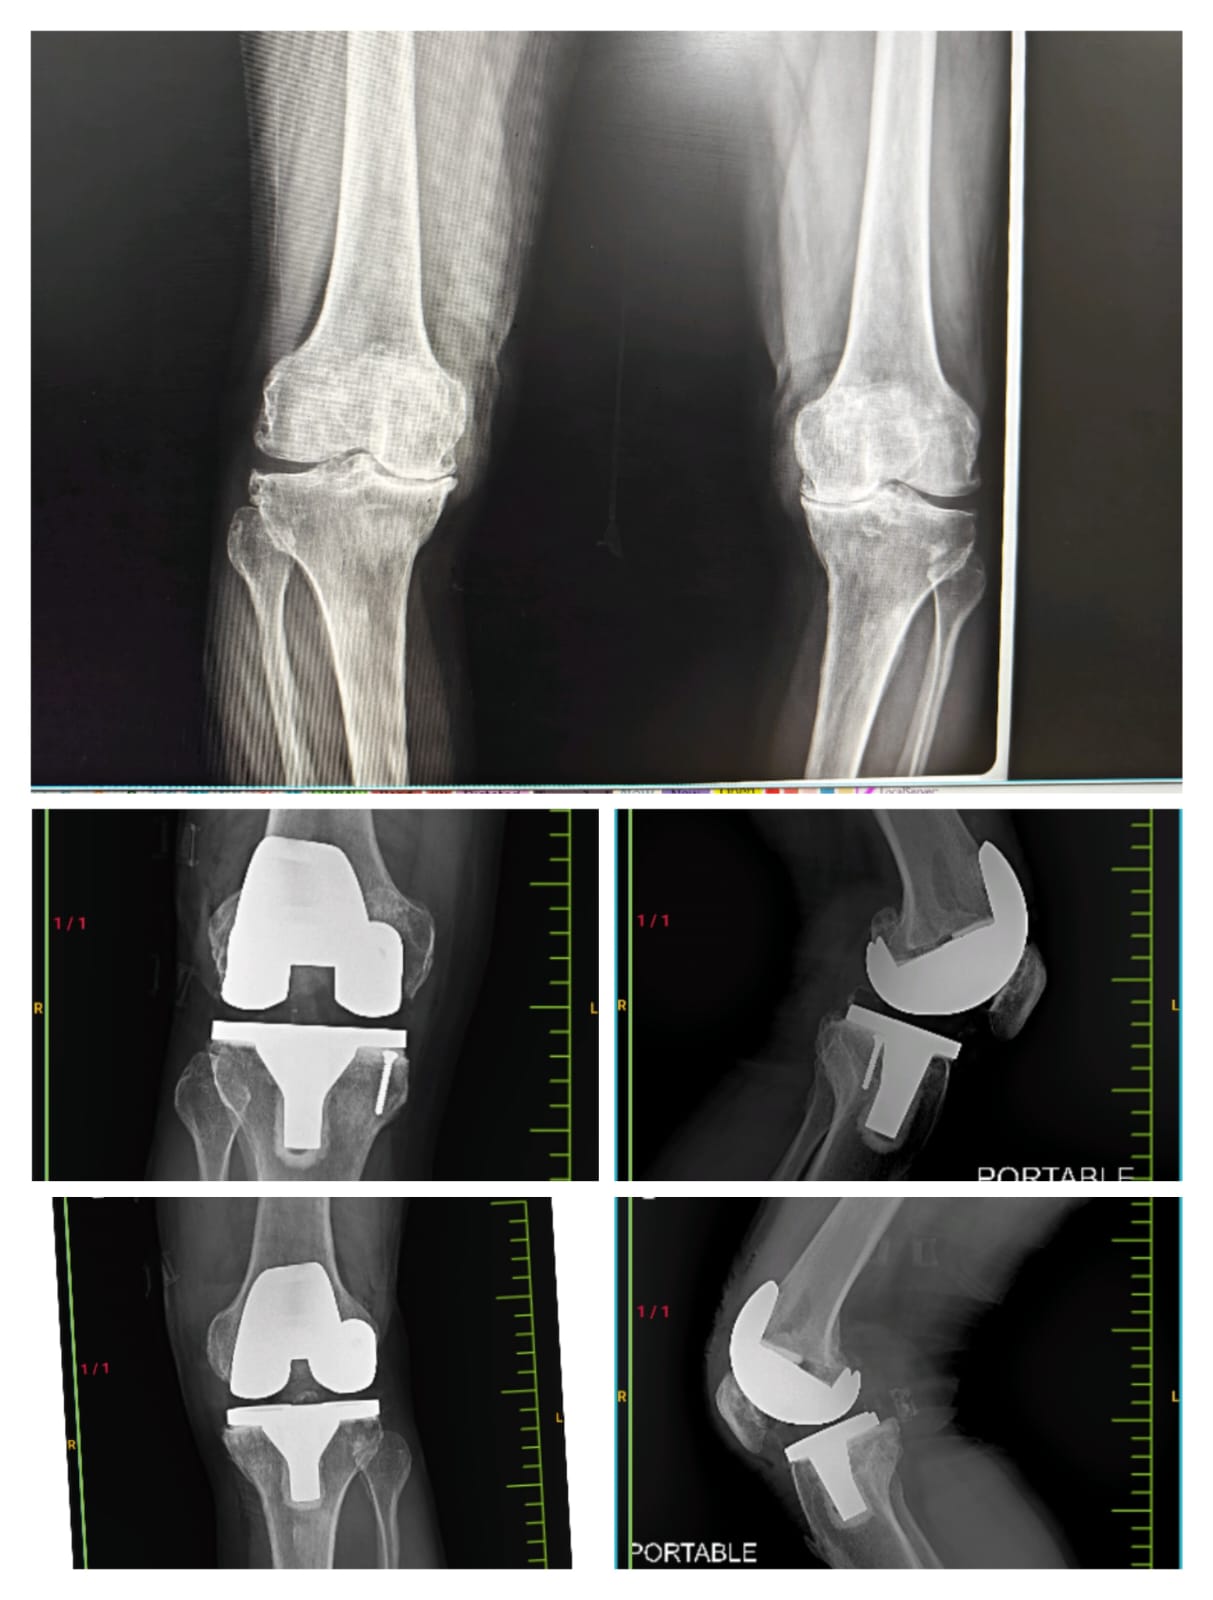

Case study